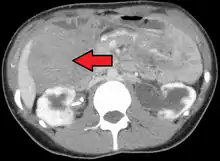

![]() | |

| Desmoid tumor as seen on CT scan | |